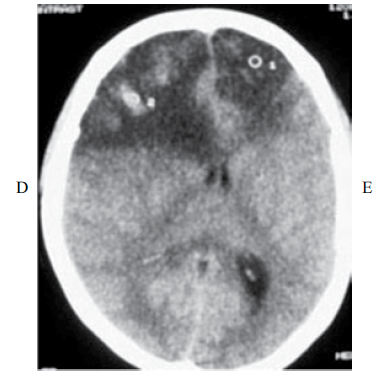

Paciente com 22 anos de idade foi admitida a serviço de emergência devido a comprometimento do nível de consciência há um dia. Ao exame físico, estava febril (39 °C), pressão arterial 70x50 mmHg, comatosa, sem resposta aos estímulos nociceptivos, pupila direita midriática. A família refere que a paciente se queixava de cefaleia há três dias. Como antecedentes, a paciente estava em tratamento com azatioprina 75 mg/dia e predinisona 20 mg/dia, devido a ulcerocolite O hemograma mostra 12 000 leucócitos/mm 3 (82% polimorfonucleares, 18% linfócitos), hemoglobina de 9 g/dL, e potássio sérico de 2.8 mEq/L. A tomografia de crânio é mostrada a seguir:

Com esses elementos, a sua primeira hipótese diagnóstica seria: